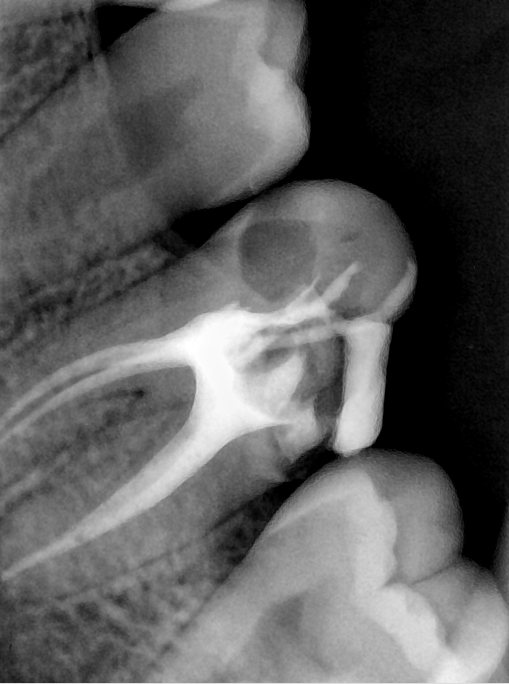

CR/DR 牙齿分割阶段记录

当前进展

- 完成了 CR/DR 牙齿相关分割训练

- 当前结果已经达到阶段预期,但仍有细节问题需要继续处理

相关测试

遇到的问题

- 训练过程中出现过 mask 下移问题

- 部分结果会出现 box 填充异常

- mask 边缘仍然有比较明显的锯齿感

参考